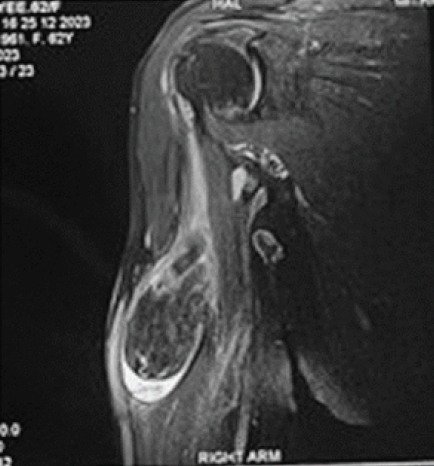

A 67-year-old female with complaints of painless swelling that progressively increased in size in the right shoulder and proximal arm for the past 8 months examination showed a palpable mass of size 8 × 5 cm non-tender with smooth surface and in the deeper planes of the shoulder girdle, mobile with firm consistency. All the shoulder movements were preserved. Plain radiographs of the right shoulder and arm were normal. Ultrasonogram showed an echogenic lesion with fluid collection in the biceps muscle plane and anterior aspect of the upper third of right arm. Magnetic resonance imaging (MRI) of the right shoulder and arm showed a well-defined space-occupying lesion of size 25 × 33 × 60 mm in the long head of biceps muscle with incomplete rupture of long head of biceps tendon at the level of supra glenoid tubercle (Fig. 1).

Figure 1: Magnetic resonance imaging of the right shoulder coronal section showing a space occupying lesion in long head of biceps. Proton density fat saturation image showing a well-defined ovoid hypointense lesion of size 6.4 cm × 3.2 cm with mild fluid seen around the mass likely of lipoma.

The lesion showed iso-intensity with fat in T1-weighted images and suppression with heterogeneous signals on T2-weighted images (Fig. 2).